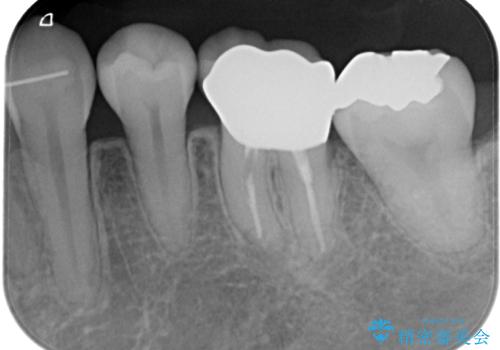

- 矯正治療が終了し、歯並びが整ったことで左下の銀歯が目立つことを気にされてご来院されました。

「せっかく矯正できれいになったので、銀歯も自然な白い歯にしたい」というご希望でした。

患者様は根管治療のやり替えは希望されなかったため、ファイバーコア+オールセラミッククラウンによる補綴治療を行いました。